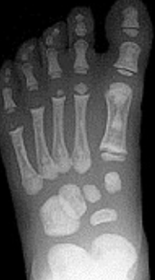

| Describe the alignment of metatarsal 2 | There is no angulation nor displacement of the distal segment relative to the proximal segment. |

| Describe the alignment of metatarsal 3 | The distal segment is displaced laterally (50% apposition) and angulated medially. |

| Describe the alignment of metatarsal 4 | The distal segment is displaced laterally (75% apposition) but there is no apparent angulation. |

| Describe the tubulation of the metatarsals | Metatarsals are overtubulated - decreased girth. |

| Describe the tubulation of the metatarsals | Metatarsals are undertubulated - increased girth. |